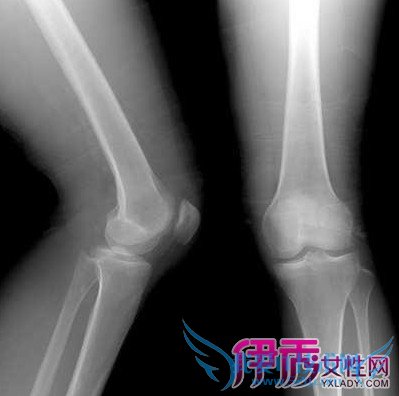

6.至6周,屈曲达100度. 三, 后期 (6-12周).1. 8周120度.2. 加强各项力量练习.3. 12周,屈膝角度基本同健侧.你好~根据你的描述,建议你指导患者进行功能锻炼时,应根据患者的体质,病情等情况逐渐增加锻炼的幅度与强度,同时要密切观察,确保安全,防止摔伤发生其他部位骨折.髌骨骨折后,直接波及到膝关节,伤后如何及时正确处理好骨折,是关系到今后膝关节功能活动的重要问题,并直接影响患者今后的工作及日常生活.因此处理应慎之.笔者认为尽量避免手术治疗,能采用手法复位,小夹板固定者,应积极采用.能采用抓髌器复位固定者,即采用此法.这样能最大限度减轻膝关节结构破坏,对功能活动的恢复有极大好处.运动疗法:髌骨骨折,在早期手法复位,夹板,包膝圈固定或抓髌器固定加托板保护固定后,宜早期下床直腿运动,行走锻炼,这样可避免废用性肌萎缩.也可避免今后下地活动时患肢肿胀,为后期功能恢复打下良好基础.

你好~根据你的描述,建议你指导患者进行功能锻炼时,应根据患者的体质,病情等情况逐渐增加锻炼的幅度与强度,同时要密切观察,确保安全,防止摔伤发生其他部位骨折.髌骨骨折后,直接波及到膝关节,伤后如何及时正确处理好骨折,是关系到今后膝关节功能活动的重要问题,并直接影响患者今后的工作及日常生活.因此处理应慎之.笔者认为尽量避免手术治疗,能采用手法复位,小夹板固定者,应积极采用.能采用抓髌器复位固定者,即采用此法.这样能最大限度减轻膝关节结构破坏,对功能活动的恢复有极大好处.运动疗法:髌骨骨折,在早期手法复位,夹板,包膝圈固定或抓髌器固定加托板保护固定后,宜早期下床直腿运动,行走锻炼,这样可避免废用性肌萎缩.也可避免今后下地活动时患肢肿胀,为后期功能恢复打下良好基础.